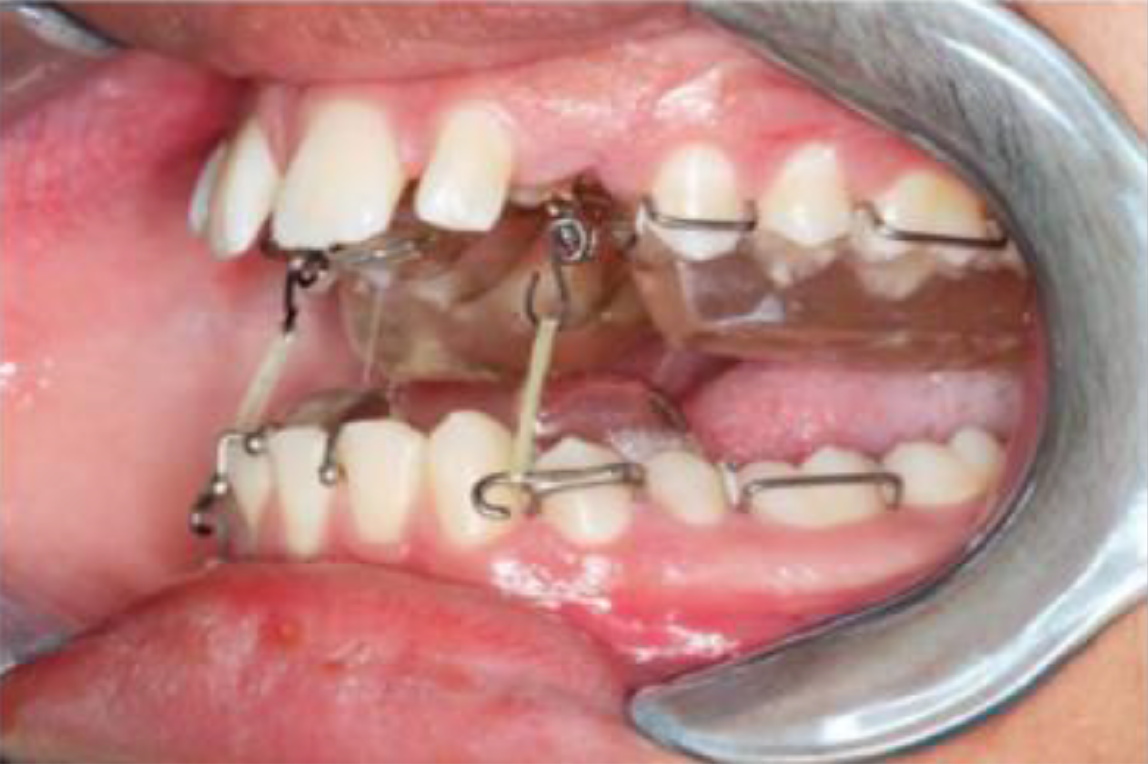

Figure 4 Modified twin block.

Extended hooks on the lower block for traction of maxillary canines and beta titanium hooks bonded to the exposed canines.